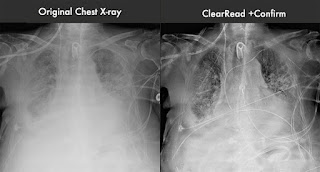

Tecnologías Riverain presentó en diciembre de 2012 su software ClearRead + Confirme, una Aplicación que mejora la claridad visual de imágenes de rayos X en Tórax convencionales, poniendo de relieve los tubos y líneas que de otro modo serían muy difíciles de ver.

La calidad de imagen es a menudo sub-óptima, pero esta empresa con su ClearRead + Confirmar procesa la radiografía, la creación de una segunda imagen del tejido blando con supresión de densidad osea de costillas y clavículas y aumentando el contraste, la nitidez y la visibilidad de los tubos, líneas y cables cardíacos.

En un estudio que evalúa el efecto del software en tiempo de lectura, 334 radiografías de tórax fueron revisados por 10 radiólogos con y sin el ClearRead. El tiempo de lectura se redujo en casi un 19 por ciento, y los lectores estaban más seguros de sus resultados. El sistema ClearRead + Confirmar ha recibido la Marca CE y está bajo revisión por la FDA.